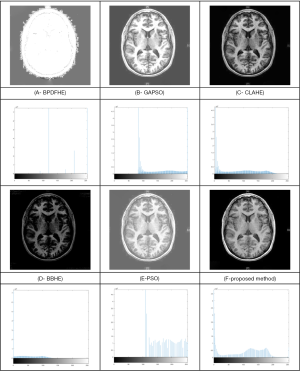

From Table 2, it can be observed that using the presented method has a greater and more extensive ability for improving contrast enhancement when compared to the other methods. The only method which does a slightly better job in skin cancer and for edge content is CLAHE. However, it is essential to know that a trade-off between the edge content and the entropy is required to choose the best method. In Figure 5, co-occurrence matrix offset in 4 directions and 4 distances is presented.

Simulation results for the analyzed images are shown in the Figures 6-9.

From Figure 6, it can be seen that the BBHE method is inapplicable for skin cancer due to its inappropriate histogram.

The obtained results by BPDFHE and PSO are suboptimal because of the gathering in their histogram in the left-hand side, which indicates a dark intensity in their images. The results of the GAPSO are better than the above methods, and have a distributed histogram, but the ROI for skin cancer (i.e., melanoma) has a very weak brightness which makes the subsequent steps fail in terms of cancer detection and the other image processing operations. However, the CLAHE method here shows better results than the others and is an excellent method. However, our proposed method achieves an ideal histogram of two peak values, thus indicating its superiority over the CLAHE method, especially during the thresholding process.

Figure 7 shows the experimental results of the brain tumor. In this example, the BPDFHE has the worst histogram and consequently, the worst contrast. The results of PSO and GAPSO are close to each other, as their histograms both gather to the right-hand side, which means they increase the brightness of the image with no useful results. The results for the BBHE show the opposite results of the prior methods; it gathers towards the left-hand side of the histogram bar. From these findings, the proposed method, along with the CLAHE method, has the best results for the brain tumor.